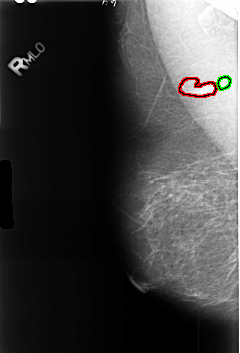

B_3444_1.RIGHT_MLO

FILE: B_3444_1.RIGHT_MLO.OVERLAY

TOTAL_ABNORMALITIES 2

ABNORMALITY 1

LESION_TYPE MASS SHAPE LYMPH_NODE MARGINS N/A

ASSESSMENT 2

SUBTLETY 3

PATHOLOGY BENIGN_WITHOUT_CALLBACK

TOTAL_OUTLINES 1

BOUNDARY

ABNORMALITY 2